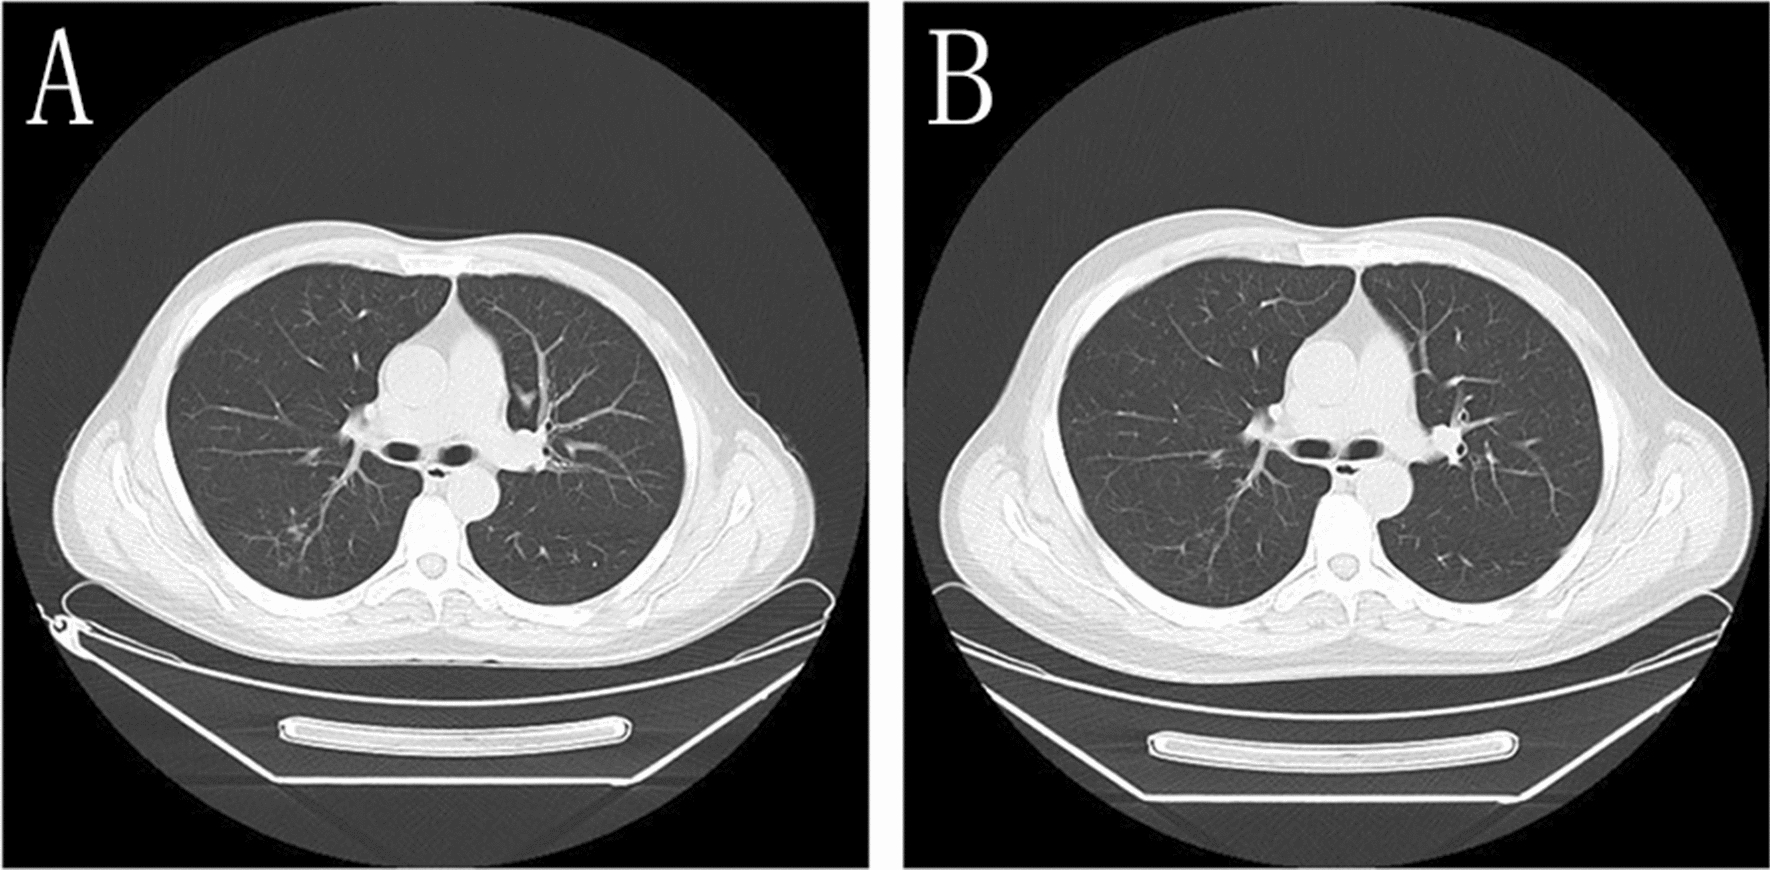

In addition, the BALF-GM test result was positive. Based on the patient’s symptoms, signs, laboratory tests, and past treatment reactions, the diagnosis was corrected to CNSAG, invasive pulmonary aspergillosis (IPA), and AIDS. Voriconazole (intravenous drips of 6 mg/kg/day q12-h on the first day, followed by intravenous drip of 4 mg/kg/day q12-h) was administered for antifungal treatment. Due to the interaction between voriconazole and EFV, the antiviral treatment regimen was revised to 3TC, TDF, and dolutegravir (DTG). After 2 weeks of this treatment, the patient’s ghosting vision and facial anhidrosis were relieved. The routine examination of cerebrospinal fluid revealed normal biochemistry. His cranial MRI indicated that the lesions in the frontal lobe were absorbed, and the surrounding edema was alleviated (Fig. 2). The patient was discharged and continued on oral voriconazole treatment (200 mg/kg/day). After 6 weeks of antifungal treatment, the patient's ghosting vision and facial anhidrosis were significantly relieved. Re-examination of his cranial MRI indicated that the lesions in the frontal lobe were significantly absorbed and improved, and the surrounding edema was alleviated (Fig. 2). His chest CT showed focal absorption (Fig. 3).

Fig. 3.

Chest CT A Before treatment, the lung tissues seemed scattered with patchy, strip-shaped shadows, nodule-like and increased acinar nodular shadows with uneven density and some unclear boundaries were noted. B After 6 weeks of treatment, chest CT showed that the lesions were resolved